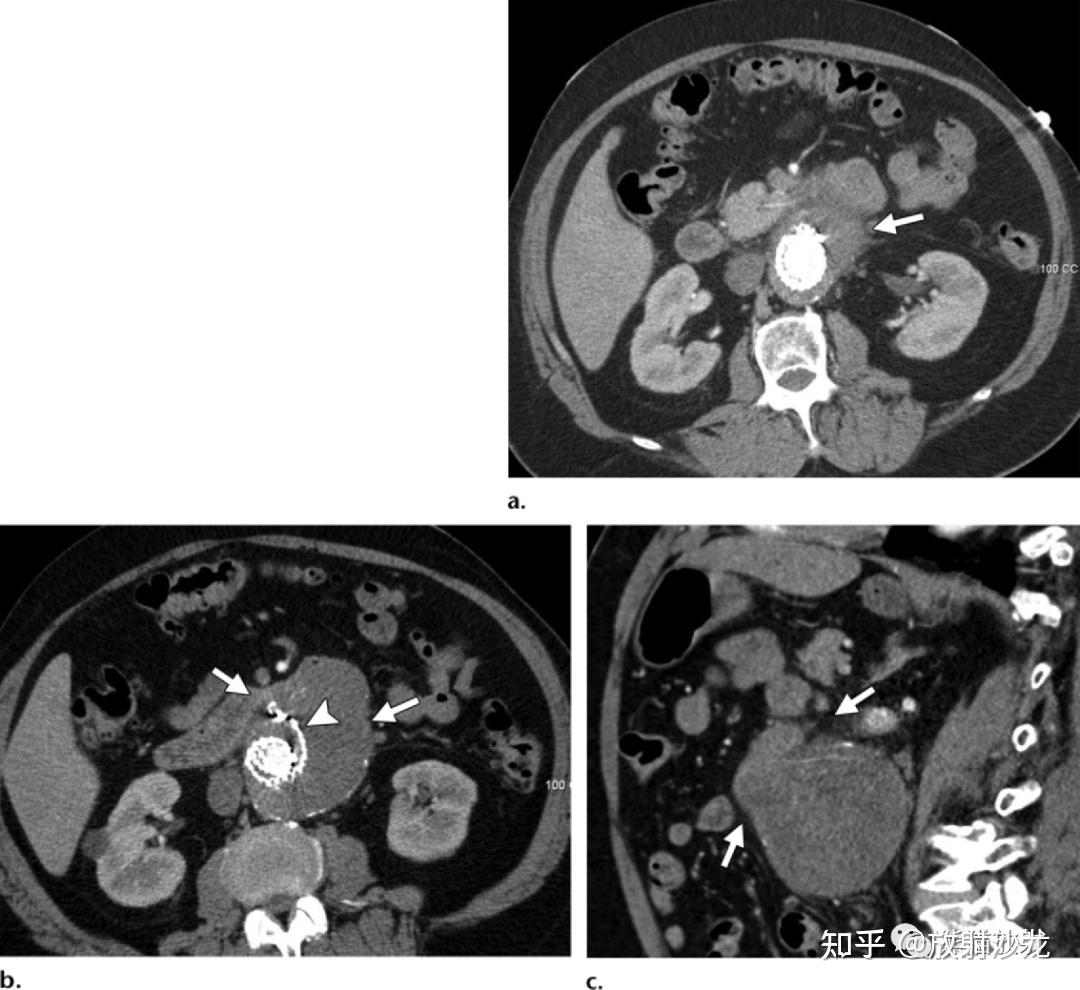

腹主动脉瘤ct表现图

腹主动脉瘤的随访哪些ct征象提示其不稳定性

cta显示动脉瘤整体面貌ct断层显示动脉瘤最大直径可达10cm腹主动脉

腹主动脉瘤破裂及先兆破裂的ct表现.ppt